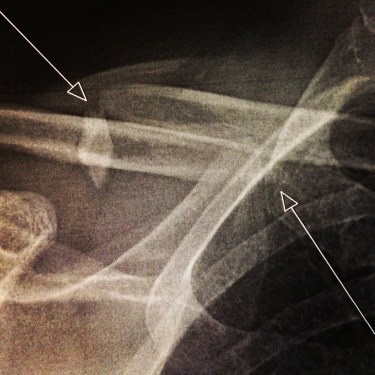

Good news though, the hubby’s collarbone is all fixed now and he is moving about. He landed up with a plate holding his collarbone together.